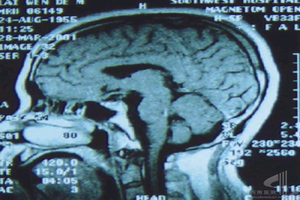

MRI檢查與CT的效果相仿,但可在橫、冠、矢3相檢查,腦脊液為更長T1及T2。

5.CT掃描及磁共振成像高分辨力的CT冠狀位掃描或磁共振成像能迅速而又無創傷地作出診斷。典型圖像示鞍窩擴大,垂體萎縮變形,被充滿與鞍上池同樣低密度的腦脊液取代。若作造影劑強化直接冠狀位CT掃描,則未見增強。重症患者垂體嚴重受壓,被推移至後下方呈薄片狀,垂體柄可深達鞍底,形成特徵性的“漏斗征”(infundibulum)。